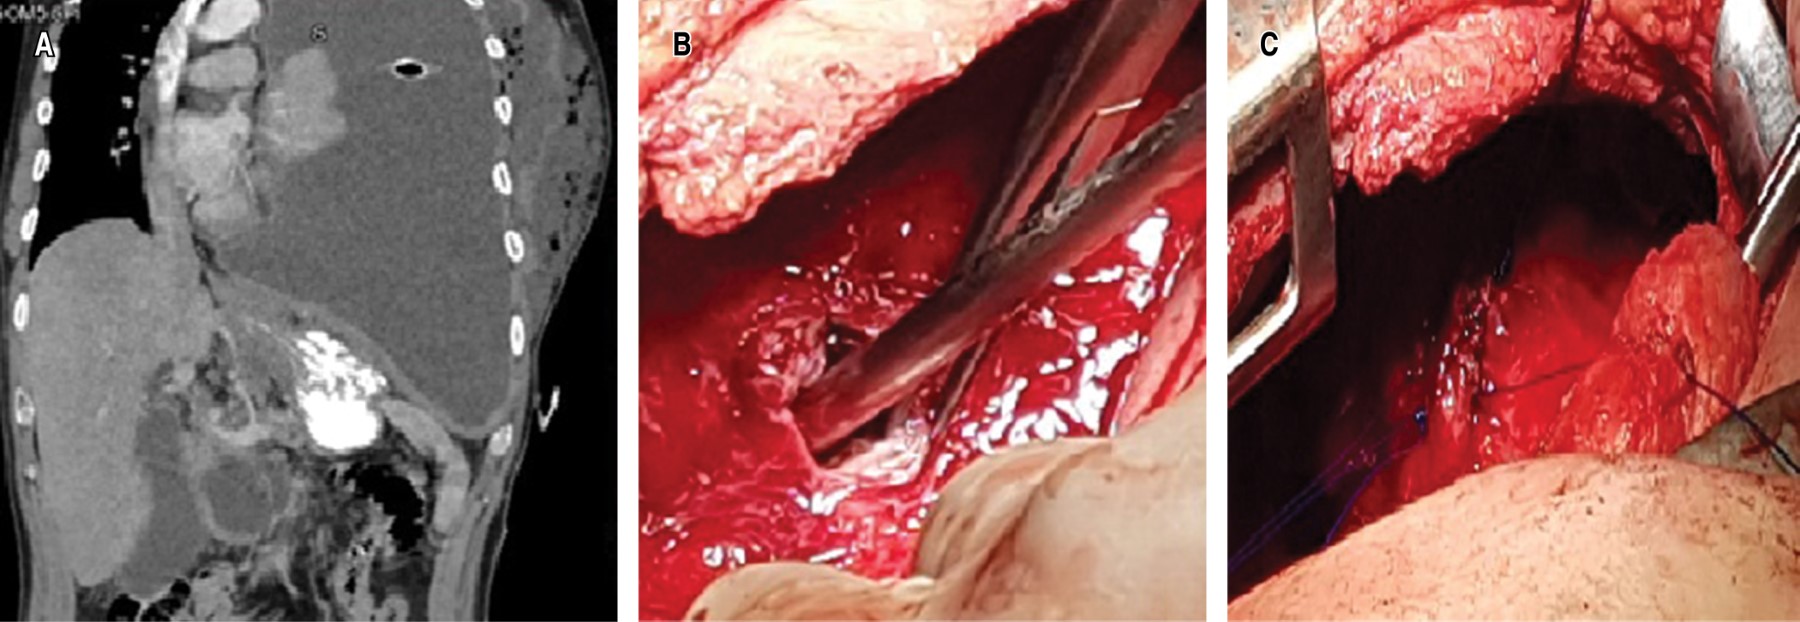

Clinical case 1. 39-year-old man, with a history of chronic alcoholism, with episodes of recurrent abdominal pain. His condition began three months prior to his admission, with pleuritic pain in the left hemithorax, progressive dyspnea and attack to the general condition; a chest X-ray was taken in which pleural effusion was identified. A thoracentesis was performed and a thick, dark pleural fluid was obtained, which, upon cytological and cytochemical analysis, showed amylase levels of 16,043 U/L and Light criteria for neutrophilic exudate. Subsequently, on performing computed axial tomography (CT) of the thorax and abdomen (Figure 1A), free fluid communication of the abdomen with the left hemithorax was identified, so it was decided to take the patient to the operating room to perform posterolateral thoracotomy; Parietal pleura was found to be 8 mm thick and visceral pleura 5 mm thick, abundant fibrin material and pus in the cavity, a fistulous tract between the abdominal cavity and left diaphragm of 1 cm in diameter (Figure 1B), with a collection of 100 mL of whitish liquid. Lavage and decortication were performed until adequate pulmonary expansion was achieved, the fistulous tract was debrided; edges were identified and the defect was closed with nonabsorbable 2/0 polypropylene suture (Figure 1C); pulmonary reexpansion was verified. After the treatment, the patient had an adequate clinical evolution; the endopleural drains, with serohematic output that decreased until their removal five days after the procedure. A control CT scan was performed, which showed a decrease in the initial pancreatic collection. After evaluation by the Gastroenterology Service, conservative management was left. At six months of surveillance with CT of the thorax, without evidence of complications.